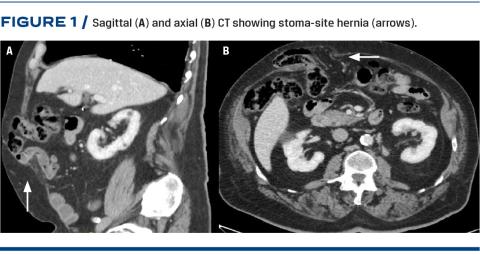

The review of CTs took place between March and April 2018. The latest CT was reviewed on all included patients in order to identify whether any incisional hernia was present at the former stoma site. All CTs were performed while the patient was in a supine position and receiving intravenous contrast fluid (Figure 1). Since the CTs were performed to look for recurrence of malignancy, a standard hernia CT protocol with patients performing the Valsalva manoeuvre was not used.